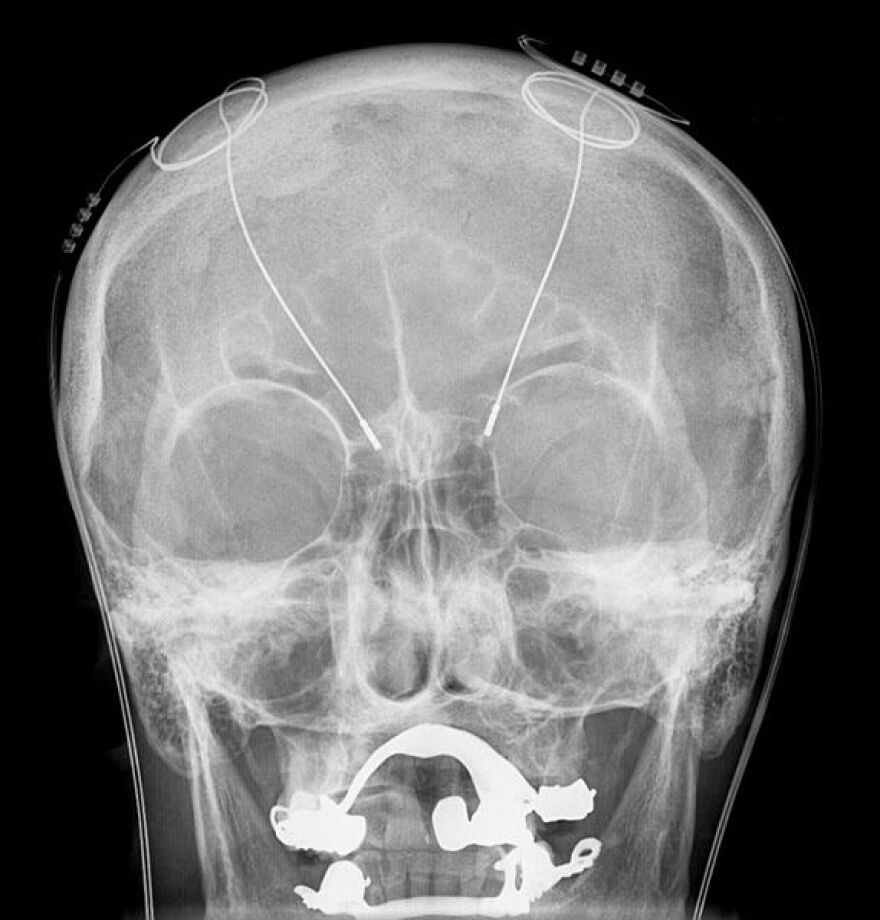

DBS-probes shown in X-ray of the skull (white areas around maxilla and mandible represent metal dentures and are unrelated to DBS devices

Here’s the plot: A man suffering from dystonia – a neurological disorder that causes twisting and abnormal postures – goes to a doctor. The doctor gives the man local anesthesia, drills into his head, inserts spaghetti-like electrodes and then hooks him up to a pacemaker to send electrical currents into his brain.

It’s not the nefarious scheme of a mad scientist but rather a pioneering medical technique called of deep brain stimulation. According to Dr. Andres Lozano, chair of neurosurgery at the University of Toronto, it’s been used on around 100,000 patients worldwide to treat ailments such as dystonia, Parkinson’s and obsessive compulsive disorder.

It works by adjusting the activities of malfunctioning brain circuits. Though it’s pretty safe – Lozano said about a 1 percent risk of a serious consequence like stroke – it’s also very precise. Patients are often kept awake to help the surgeon “find the right spot.”

“An error of one millimeter can mean the difference between having a side effect or just not working at all, so you have to be extremely precise,” Lozano told KUOW’s David Hyde on The Record.